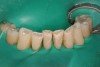

A number of studies have investigated the ability to light-cure composite resins based on the position of the curing light.43-45 While many preparations provide for excellent clinical access for curing lights, there are hard-to-reach areas of the oral cavity. In some cases, the curing light tip itself is a limiting factor to how close the light can get to the surfaces being light-cured and whether or not it has the correct orientation. In fact, dentists and dental assistants (many who hold the light and activate it) are not well trained in the art and science of light-curing. One only has to read articles on clinical techniques that require light-curing to see that typically the only reference to light-curing in the article is to “light cure for (fill in a number) seconds.” The orientation of the light tip, diameter of the light tip, and type of light being used relative to energy output is rarely noted. This author’s interest in better light-curing of restorations has led to learning how to use a unique and innovative device, MARC, which is a laboratory-grade, clinically relevant, light-curing energy measurement tool. The sensors to measure the light energy delivered are embedded in a typodont head and jaws with immediate results and data collected by a chairside computer. This elegant device measures the useful light-curing energy delivered to simulated restorations. It provides immediate feedback so that one can train with the device immediately to improve one’s light-curing skills. Several research studies reported on this device made the following recommendation: to maximize energy delivered, the operator should wear eye protection, should watch what he or she is doing, and should hold the light both close and perpendicular to the restoration (Figure 1 through Figure 6).43 Placement of the light source at a less than perpendicular angle to the cavity preparation can lead to incomplete photopolymerization (Figure 7 and Figure 8).

There is a wide variety in the diameter of the light tips provided with different curing lights. While an 8-mm-wide diameter tip can meet the requirements of most restorations, there are times that a wider-diameter curing light tip is necessary. When placing sealants or composites on the occlusal surfaces for permanent molars, or light-curing the complete facial surface of an maxillary anterior tooth when placing porcelain veneers or direct composite resin veneers, a wider diameter is highly recommended. Smaller-diameter tips will require an overlapping of the tip and multiple curing areas to ensure complete polymerization of the restoration. Also, a technique that has been favored when placing porcelain veneers is the use of a small-diameter tacking tip to stabilize the veneer and allow for removal of excess resin cement before complete light-curing (Figure 9 and Figure 10). When selecting a curing light, evaluate the ability of the curing light to accept a selection of different diameters of curing tips for the variety of different restorations that are being placed.